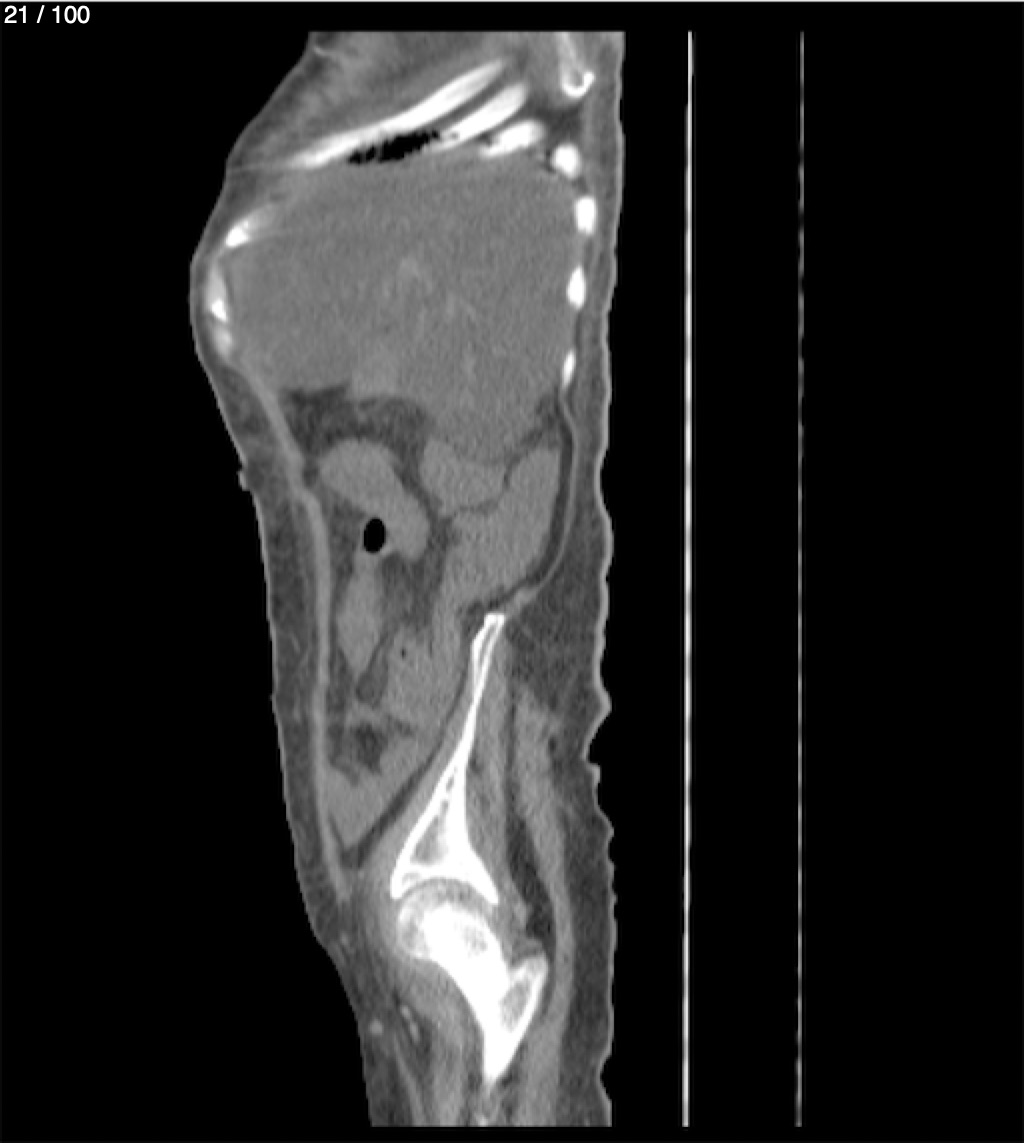

Hilda Geronimo Mendez 60A - T.C Abdomen Simple